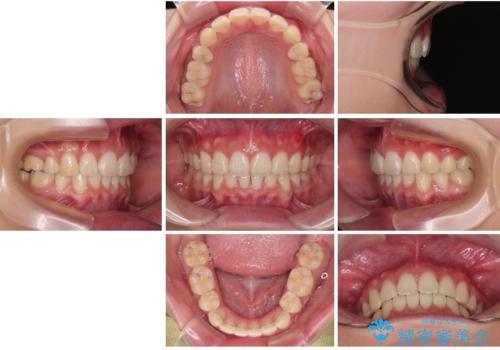

口元が出ているのを改善したい。 クリアブラケットによる抜歯矯正

- 前歯部のデコボコと口元が出ているのが気になるとのことで来院された患者様です。

口元の突出感の解消と、このままデコボコを解消するとさらに出っ歯傾向になってしまうことを考慮し、上下左右の小臼歯を抜歯しクリアブラケットにて矯正していくこととしました。

舌突出癖を改善するトレーニングを一生懸命やっていただいたおかげで2年以内に治療を終えることができました。